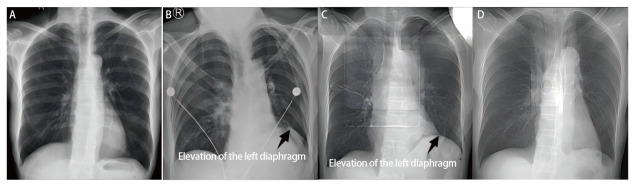

Background: Video-assisted thoracoscopic surgery (VATS) lobectomy is the primary surgical treatment for lung cancer. A significant factor affecting postoperative recovery is prolonged air leak (PAL). Despite numerous clinical strategies could prevent and manage postoperative PAL, its incidence remains high. Phrenic nerve cryotherapy (PNC) temporarily inhibits phrenic nerve function, causing diaphragm elevation, which reduces thoracic cavity volume, enhances pleural apposition, and mitigates air leakage. This study investigates the efficacy of PNC in preventing postoperative PAL during VATS lobectomy.

Results: The baseline clinical characteristics were comparable between the two groups (P>0.05). The incidence of pulmonary air leakage at 24 h after surgery (31.5% vs 29.6%) and the incidence of postoperative PAL (20.4% vs 14.8%) showed no significant differences between the two groups (P>0.05). The intraoperative air leak test to 24 hours after surgery revealed that air leakage ceased in 8 cases (32.0%) in the control group, compared to 14 cases (46.7%) in the experimental group. Moreover, during the progression from air leakage at 24 hours post-surgery to postoperative PAL, air leakage ceased in 6 cases (35.3%) in the control group and 8 cases (50.0%) in the experimental group, with a statistically significant difference (P<0.001). Compared to the control group, the patients in the experimental group exhibited more pronounced postoperative diaphragmatic elevation that recovered to a slightly higher than preoperative level by 3 mon after surgery.